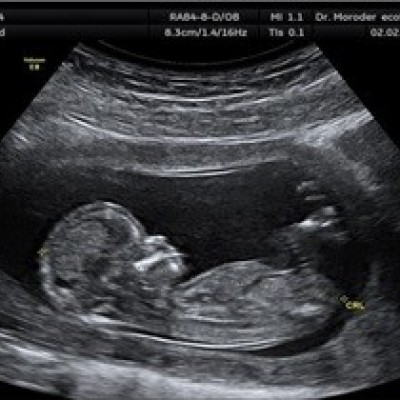

بارداری و زایمان

امکان بارداری در شرایط خاص